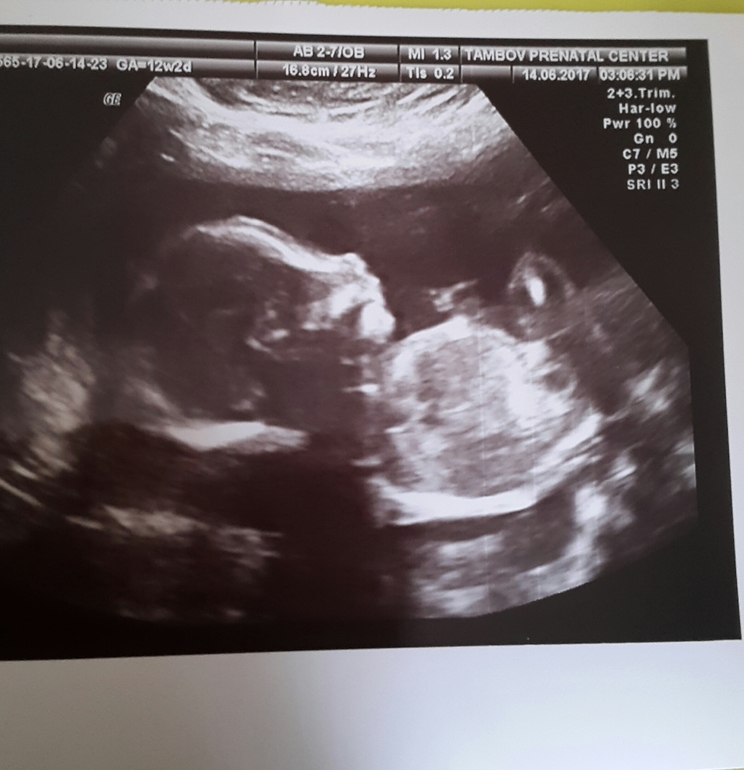

вот еще в 20 недель)

Русть оценит отдельно от первого)